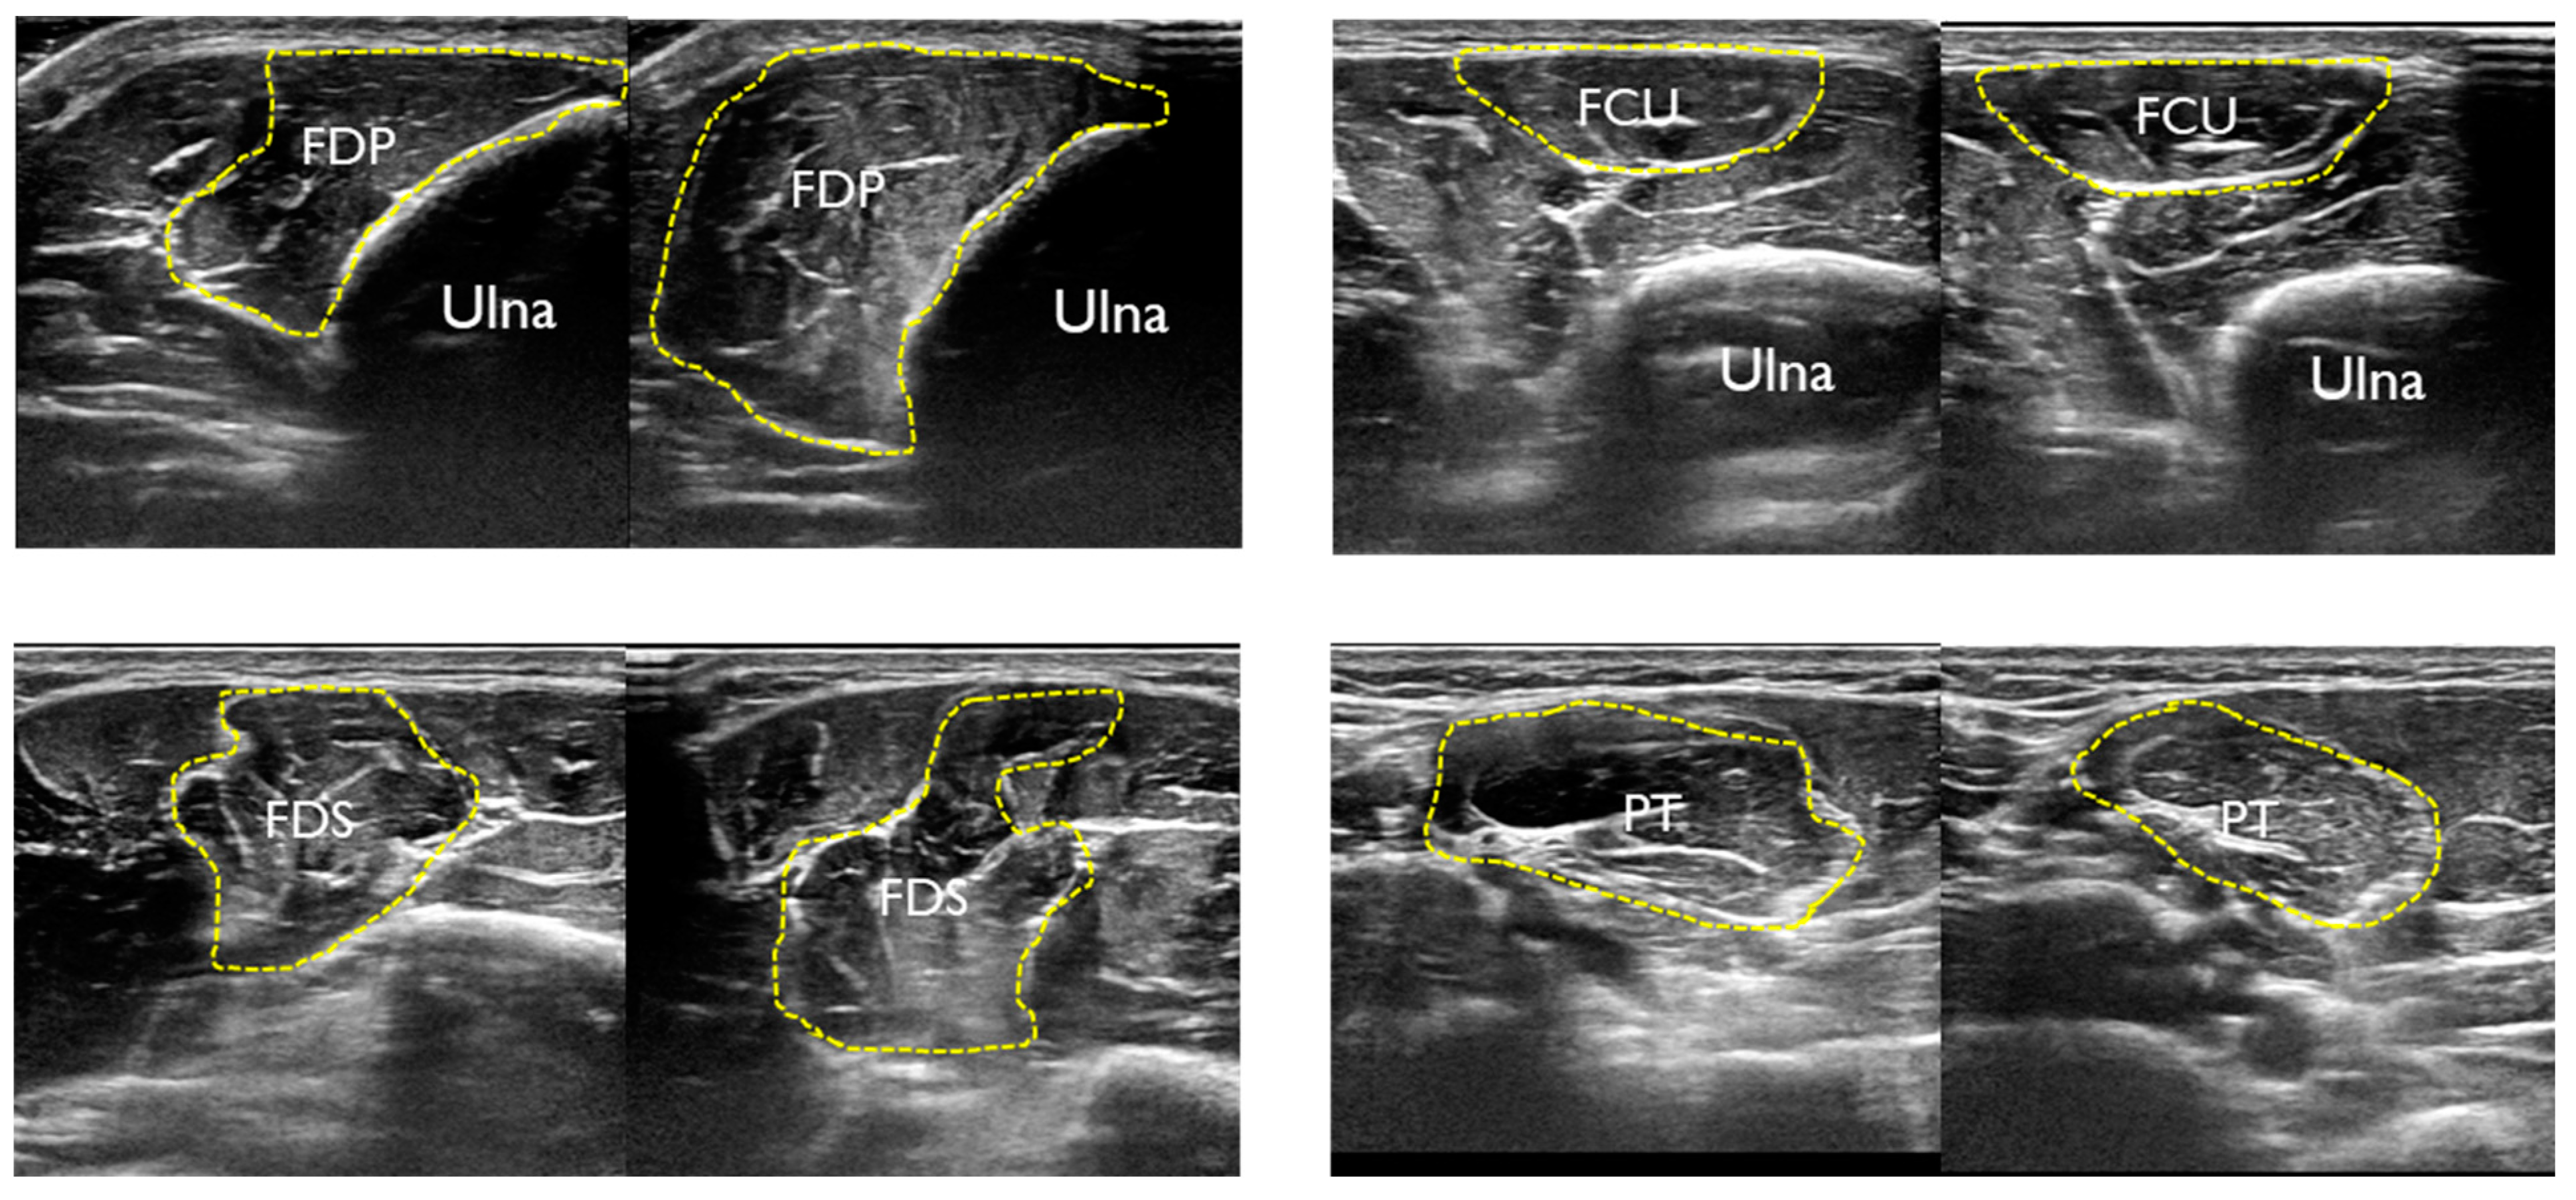

| Rest | Contraction | |||||

|---|---|---|---|---|---|---|

| ICC | 95%CI | SEM | ICC | 95%CI | SEM | |

| FDP | 0.93 | 0.69–0.98 | 0.17 | 0.89 | 0.56–0.98 | 0.20 |

| FCU | 0.99 | 0.94–0.99 | 0.05 | 0.98 | 0.92–0.99 | 0.07 |

| FDS | 0.94 | 0.76–0.99 | 0.19 | 0.94 | 0.77–0.99 | 0.13 |

| PT | 0.96 | 0.82–0.99 | 0.19 | 0.97 | 0.87–0.99 | 0.15 |

| UN | 0.90 | 0.56–0.98 | 0.005 | |||